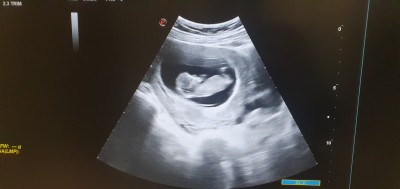

Merhaba kızlar 11+3 gunluguz cinsiyet için doktor birsey demedi aranızda tecrübeli anneler varsa bakabilir mi? Rica etsem..

Gebelik haftası 11